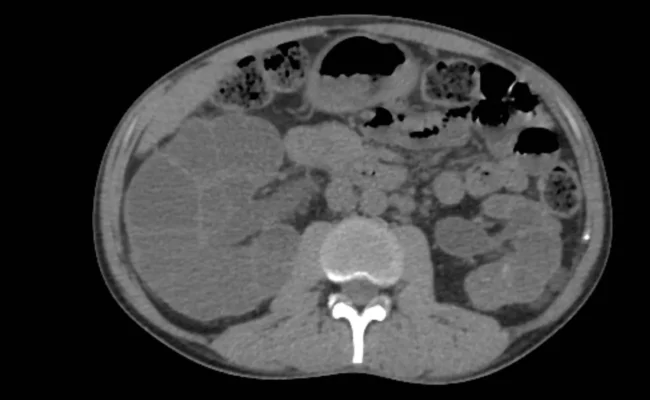

أعلن فريق من العلماء في برلين بألمانيا عن تحقيق تقدم واعد نحو علاج مرض الكلى متعدد الكيسات السائد (ADPKD)، وهو أحد أكثر أمراض الكلى الوراثية شيوعاً وتهديداً للحياة، وذلك بالاعتماد على تقنية تعديل الجينات الدقيقة.قاد الدراسة الدكتور مايكل كامينسكي، ونُشرت نتائجها في مجلة Molecular Therapy. استخدم الباحثون تقنية تعرف باسم "تحرير القاعدة" (Base Editing)، وهي…